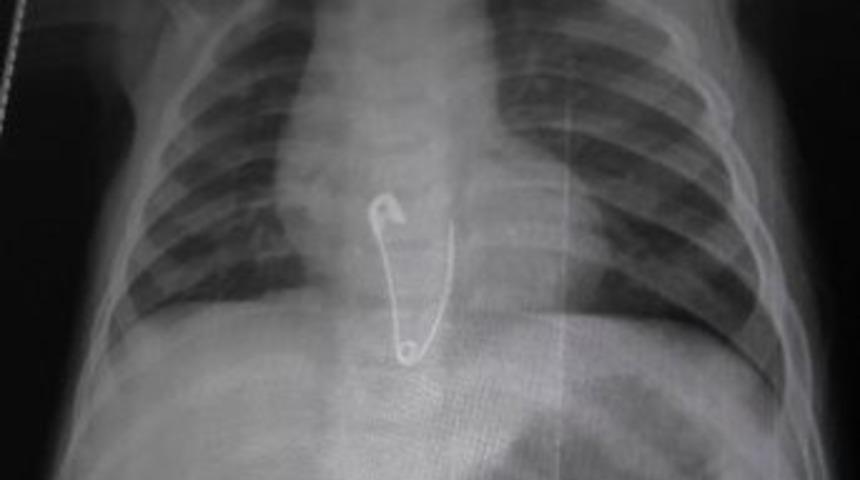

Çengelli İğne Yutan 8 Aylık Bebek Hastanelik Oldu

Konya’nın Kulu ilçesinde çengelli iğne yutan 8 aylık bebek hastaneye kaldırıldı.Edinilen bilgiye göre, 8 aylık olan T.N.Y. evde sehpa üzerinde bulunan çengelli iğneleri alarak oynamaya başladı. Bir süre sonra ailesi tarafından fark edilen bebeğin oynağı iğnelerin eksik olduğu anlaşıldı. Yapılan aramada eksik olan çengelli iğneyi bulamayan aile, çengelli iğneyi bebeklerinin yutmuş olabileceğini düşünerek Kulu Devlet Hastanesi’ne başvurdu. Çekilen röntgende çengelli iğnenin bebeğin yemek borusunda olduğu belirlendi. Bunun üzerine 8 aylık bebek iğnenin çıkarılması için Ankara’ya sevk edildi.